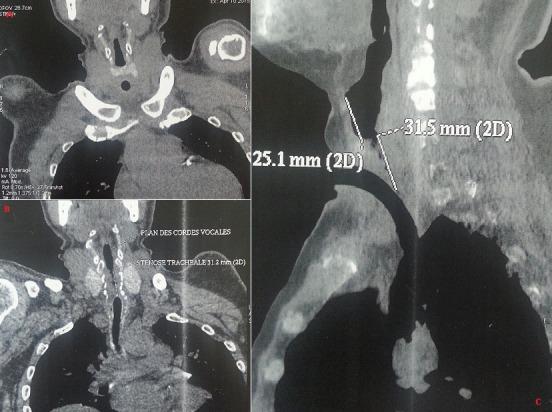

The rate of post-intubation tracheal stenosis (PITS) varies from 10 to 22% according to the studies. Only 1-2% of these stenoses are severe or symptomatic and manifest as inspiratory dyspnea that doesn't improve under corticosteroid treatment. STPI often occurs in patients with altered general status and this complicates their management. We report the case of a 43-year old hypertensive patient with a 1-year history of haemorrhagic stroke due to hypertensive peak, who had been in a coma for 3 months, requiring prolonged intubation and tracheotomy. Tracheal cannula removal had been proven time and again, but it was impossible due to respiratory distress. ENT exam showed important subglottic stenosis above the hole due to tracheotomy. Ct scan confirmed tracheal stenosis (A, B, C). Tracheoscopy under general anesthesia objectified subglottic stenosis at 1 cm from the glottic floor. The patient underwent surgery with proximal tracheal resection of 3cm, posterior cricoid mucosectomy and cricotracheal anastomosis. Postoperative outcome was favorable. The diagnosis of PITS is sometimes difficult, but it should be suspected in any patient with dyspnoea of recent onset or with unusual dyspnoea after intubation and/or tracheotomy. Tracheal resection and anastomosis, as they have been performed in our study, are the treatment of choice for tracheal stenosis.

根据研究,气管插管后气管狭窄(PITS)的发生率在10%至22%之间。这些狭窄中只有1% - 2%是严重的或有症状的,表现为吸气性呼吸困难,在皮质类固醇治疗下无改善。PITS常发生于一般状况改变的患者,这使其治疗变得复杂。我们报告一例43岁高血压患者,因高血压急症有1年出血性中风病史,昏迷3个月,需要长期插管和气管切开。气管套管多次尝试拔除,但因呼吸窘迫未能成功。耳鼻喉检查显示气管切开部位上方声门下严重狭窄。CT扫描证实气管狭窄(A、B、C)。全身麻醉下的气管镜检查发现声门下距声门底部1 cm处狭窄。患者接受了3 cm近端气管切除术、后环状软骨粘膜切除术和环状气管吻合术。术后结果良好。PITS的诊断有时很困难,但对于近期出现呼吸困难或插管和/或气管切开后出现异常呼吸困难的任何患者都应怀疑。如我们研究中所进行的气管切除和吻合术,是气管狭窄的首选治疗方法。